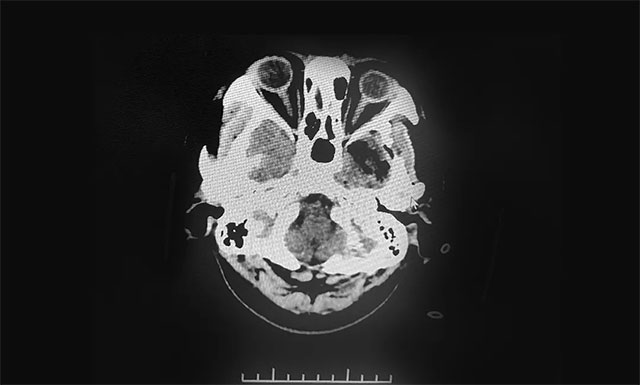

▲ 术后影像显示肿瘤被切除